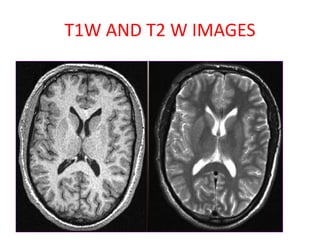

• SHORT TE

• SHORT TR

• BETTER ANATOMICAL DETAILS

• FLUID DARK

• GRAY MATTER GRAY

• WHITE MATTER WHITE

T1 W IMAGES

• MOST PATHOLOGIES DARK ON T1

• BRIGHT ON T1

– Fat

– Haemorrhage

– Melanin

– Early Calcification

– Protein Contents (Colloid cyst/ Rathke cyst)

– Posterior Pituitary appears bright on T1

– Gadolinium

• LONG TE

• LONG TR

• BETTER PATHOLOGICAL DETAILS

• FLUID BRIGHT

• GRAY MATTER RELATIVELY BRIGHT

• WHITE MATTER DARK

T2 W IMAGES

T1W AND T2 W IMAGES